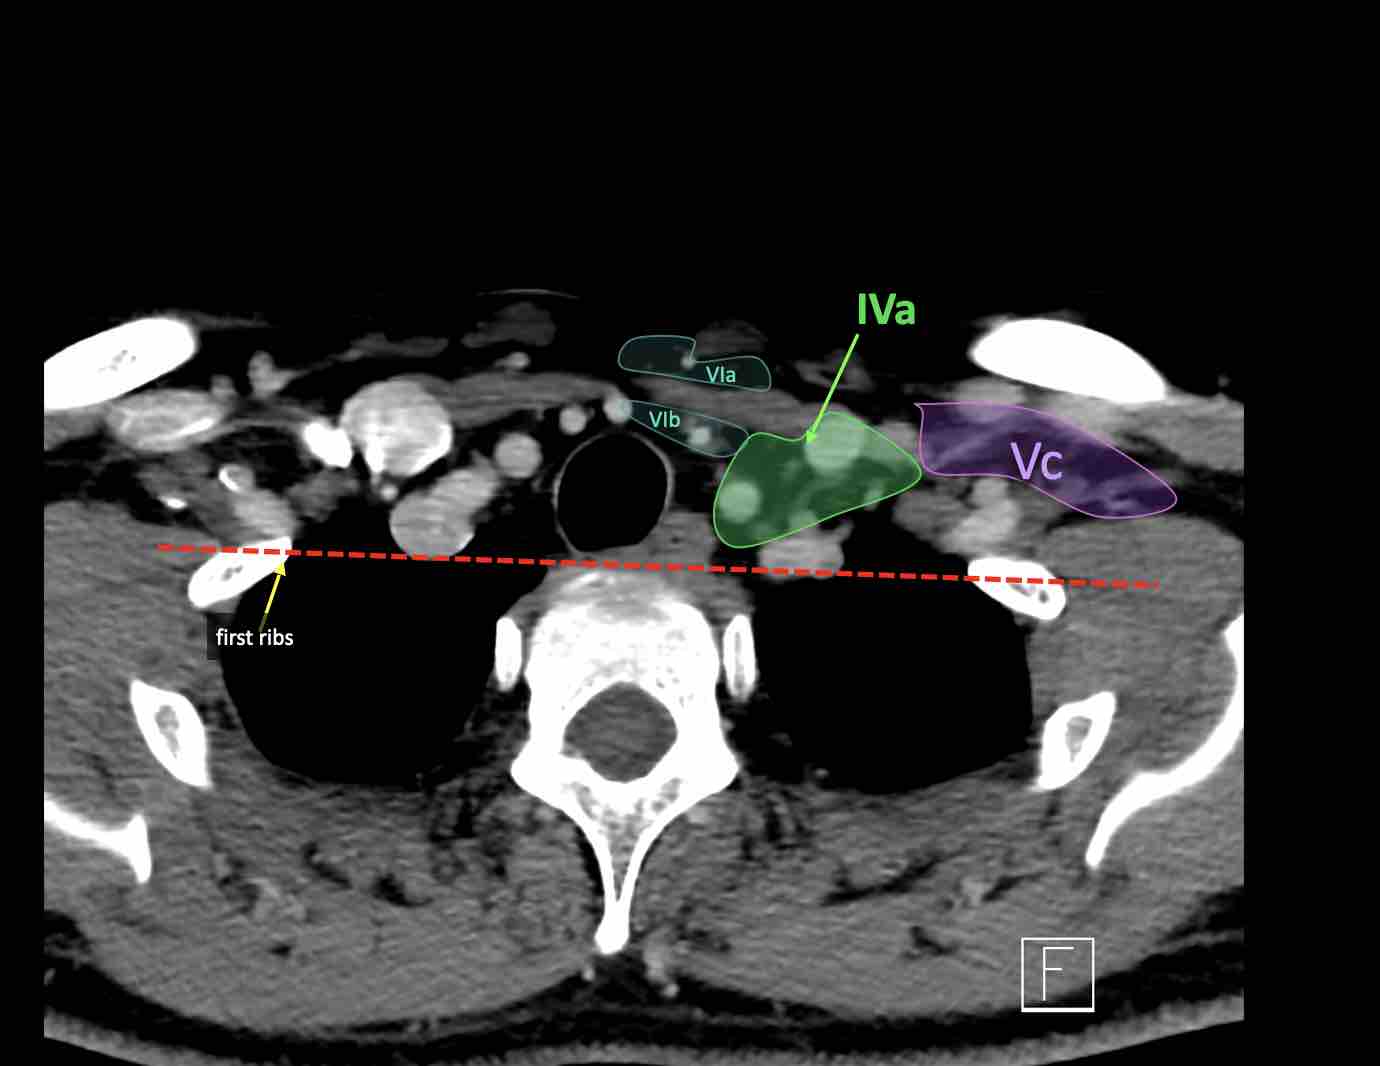

IV – Tĩnh mạch cảnh dưới và hố thượng đòn trong

Ranh giới giữa tầng IVa và IVb được xác định tùy ý tại vị trí 2 cm phía trên khớp ức đòn.

Tầng IVb

Các hạch này có nguy cơ chứa di căn từ các ung thư hạ hầu, thanh quản dưới thanh môn, khí quản, tuyến giáp và thực quản cổ.

Tầng Vc – Hố thượng đòn

Tầng này chứa các hạch thượng đòn bên nằm trong phần tiếp nối của các hạch tam giác cổ sau (tầng Va và Vb) từ các mạch máu cổ ngang xuống đến giới hạn được xác định tùy ý tại vị trí 2 cm phía trên cán ức.

Tầng này tương ứng một phần với vùng được gọi là hố thượng đòn.

Tầng Vc nhận các bạch mạch hướng tâm từ các hạch tam giác cổ sau (tầng Va và Vb) và thường liên quan hơn đến các khối u vòm hầu [1].